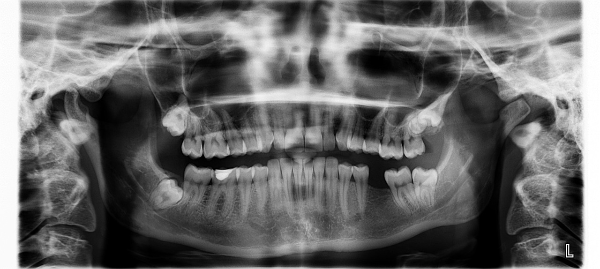

치주 질환은 치아 주변 조직인 잇몸과 지지조직에 영향을 주는 염증성 질환입니다. 주로 불규칙한 칫솔질이나 충분하지 않은 구강 위생 등으로 인해 발생할 수 있습니다. 치주 질환은 크게 gingivitis(치은염)와 periodontitis(치주염)로 나뉩니다.

치주 질환은 초기에는 치은염으로 시작할 수 있지만, 무시하거나 적절한 치료를 받지 않으면 치주염으로 진행될 수 있습니다.